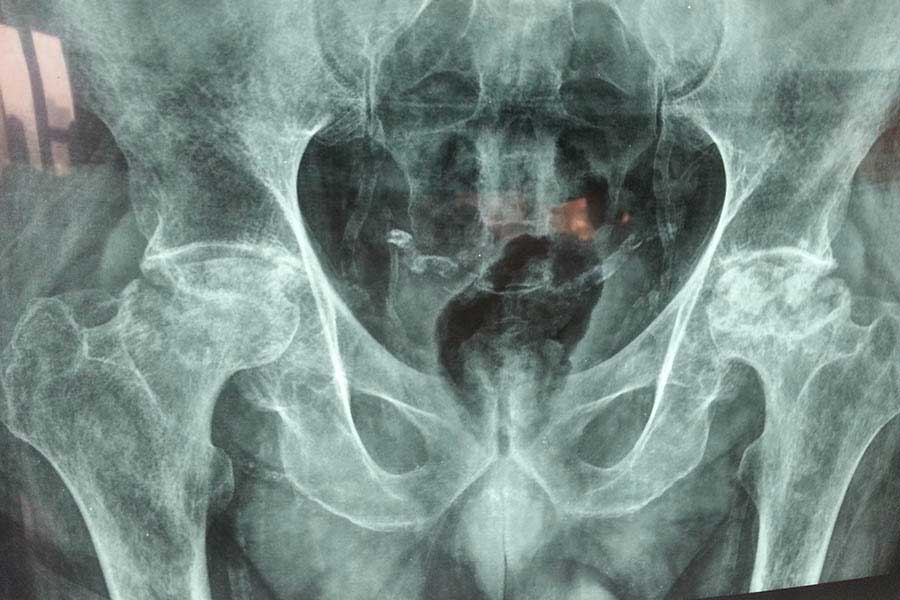

Total Hip Replacement

Difficult Replacement

Case 1